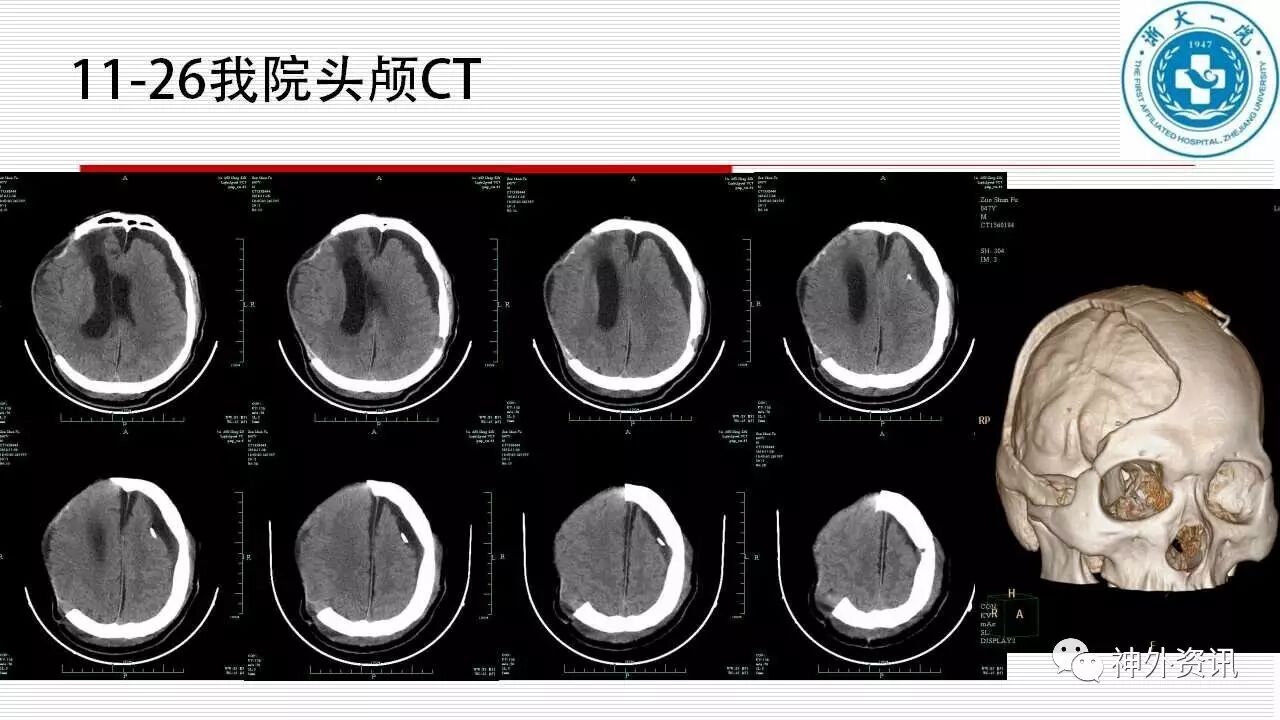

经过外引流或Omaya囊置入后穿刺抽液,可以缓解患者的症状,但症状可能反复甚至加重,部分患者甚至因此并发颅内感染导致死亡。杨小锋教授团队凭着丰富的经验及早对患者进行了颅骨修补。第一个病例经颅骨修补后得到治愈,说明颅骨修补可使去骨瓣减压导致的脑血流和脑脊液循环紊乱得到纠正恢复,恢复颅腔的密闭性是治疗的关键。第二个病例经颅骨修补后硬膜下积液消失、病情明显好转,但后来发展为脑积水,经VP分流后治愈。这说明早期的硬膜下积液有可能是脑积水的特殊表现脑室外部积水。硬膜下积液的问题还需要继续深入研究。另外也要重视去骨瓣减压术的并发症,要严格把握去骨瓣的手术指证。